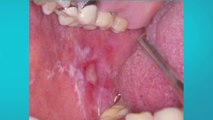

tn7-retrasos-administrativos-de-ccss-impiden-que-800-pacientes-con-cancer-reciban-diagnostico-200723